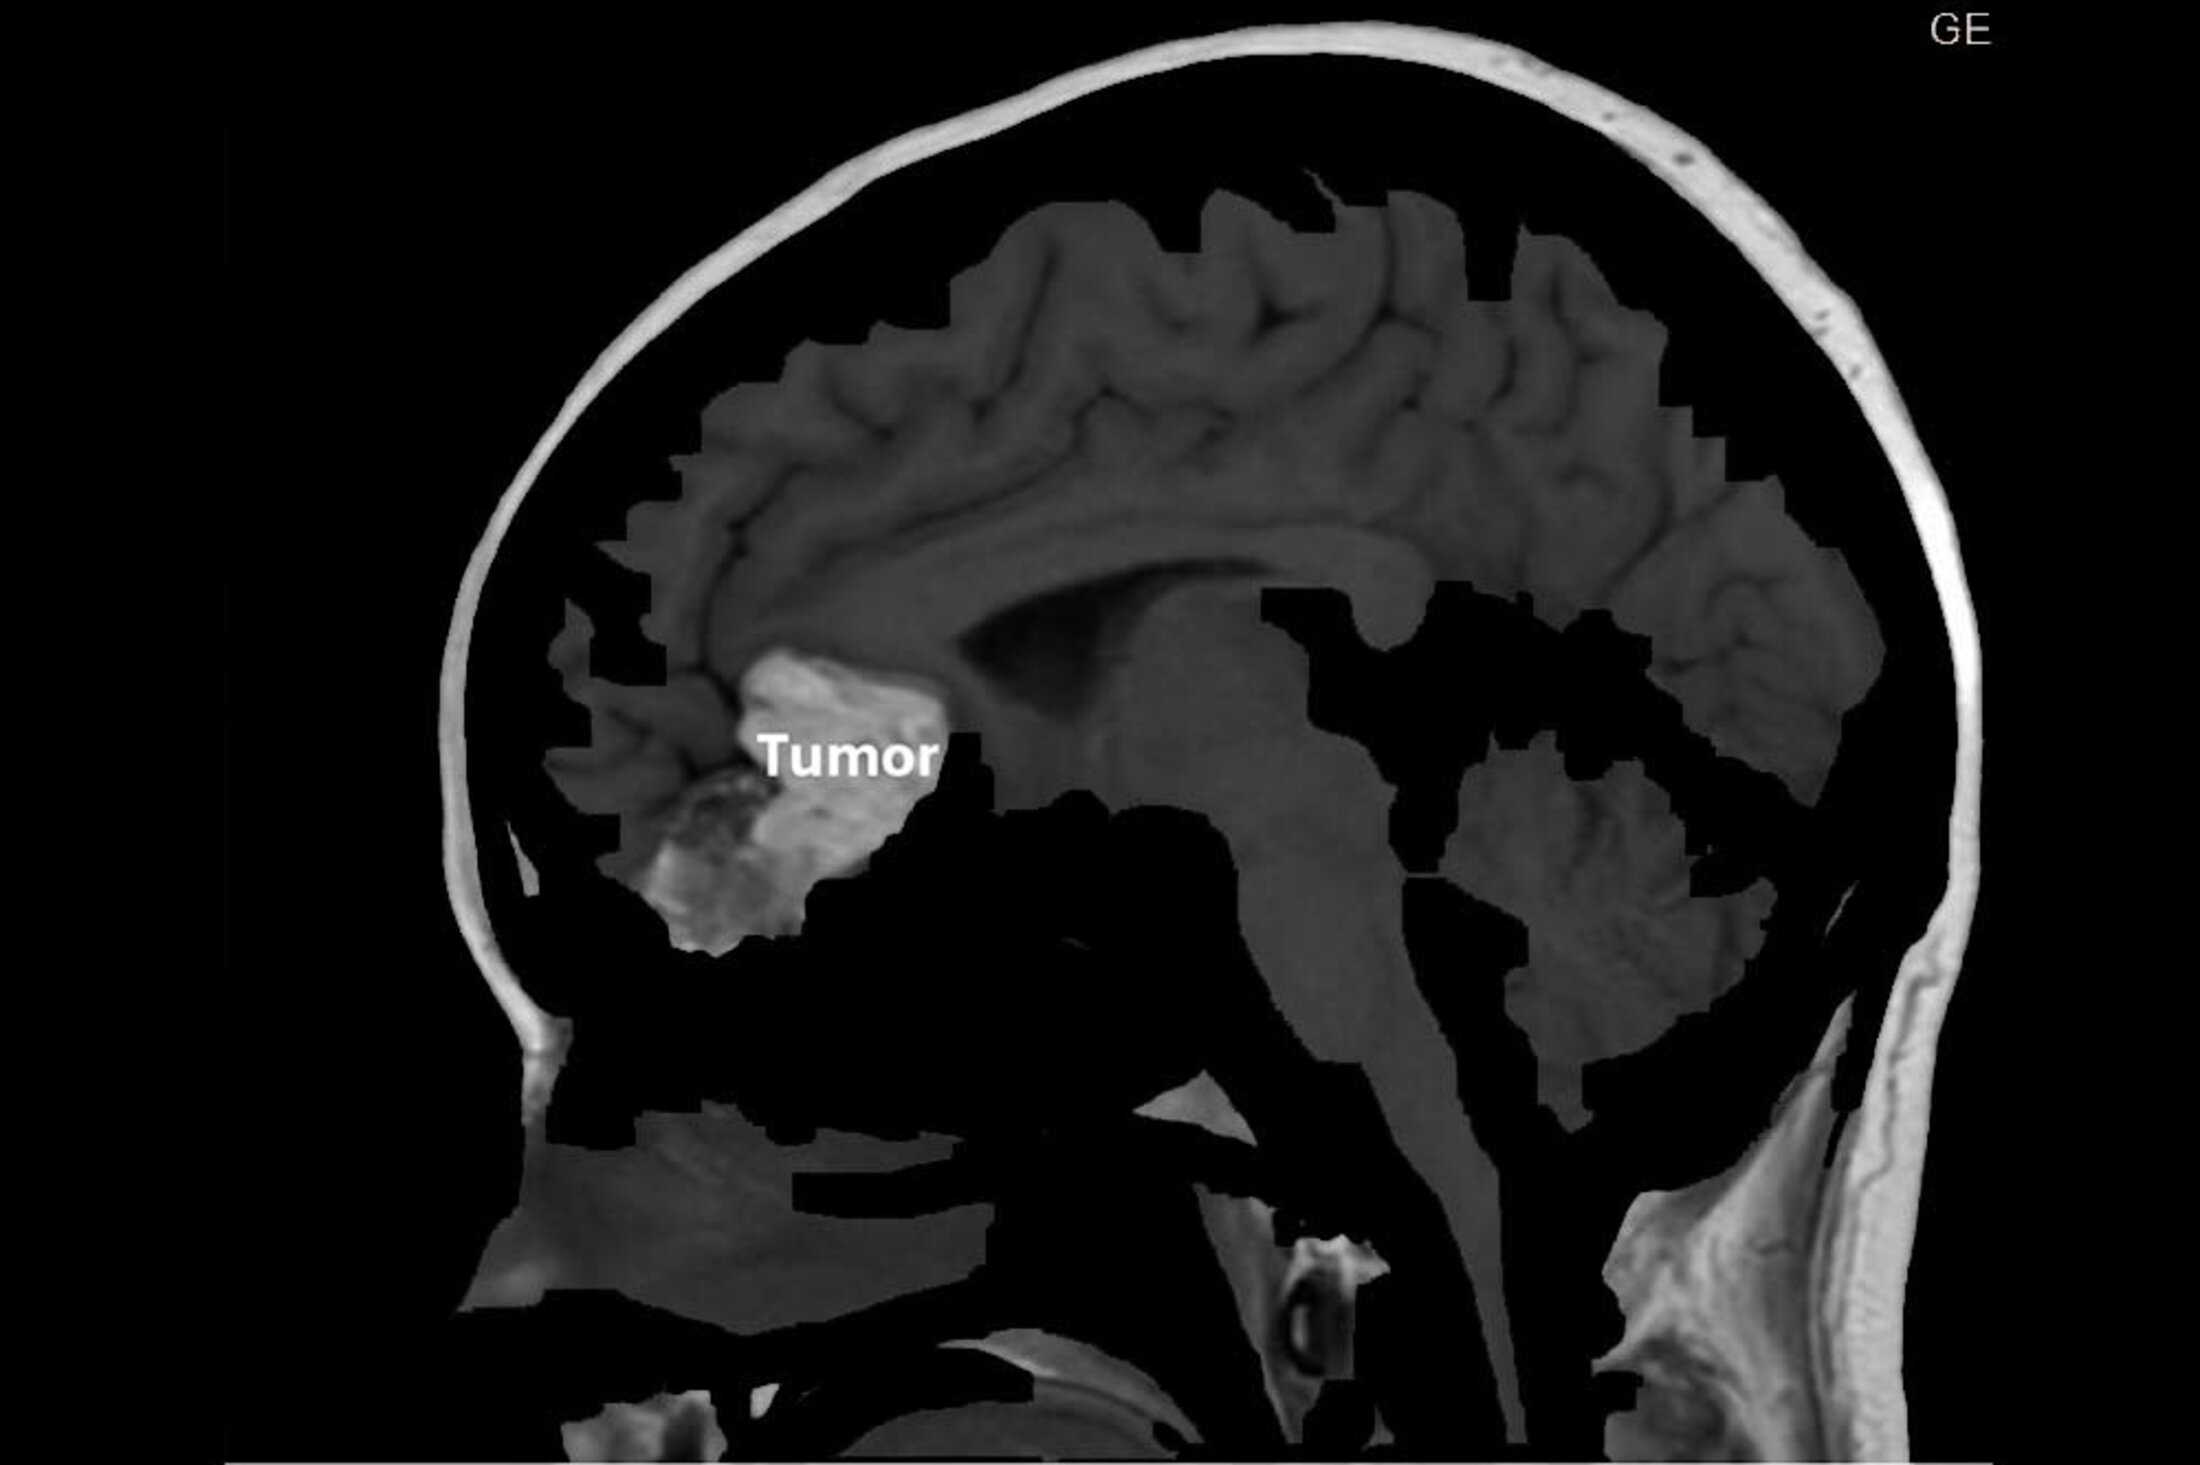

An image from neurosurgeon Dr. Jaime Martinez shows the cyst in Emily Smith's brain, a growth that formed while she was still in the womb.

“It was about the size of an egg, like a chicken egg. And it was in my frontal lobe between the two hemispheres of my brain,” Smith said.

That cyst had been there her entire life, forming when she was in the womb – likely during the early weeks after conception. MUSC Health neurosurgeon Jaime Martinez, M.D., explained how the cyst came about. “Some of the elements, such as skin, hair follicles and sebaceous and sweat glands, get trapped inside the neural tube. That's where the brain develops.”

The cyst was not cancerous. But it did need to come out, Martinez said, because of its size and the fact that it was causing symptoms, including seizures and headaches. It’s not the kind of thing he normally sees. “It's rare. It is around 0.1% of the total brain tumors. And the location of hers is also rare.”

An overview of Emily Smith's dermoid cyst.